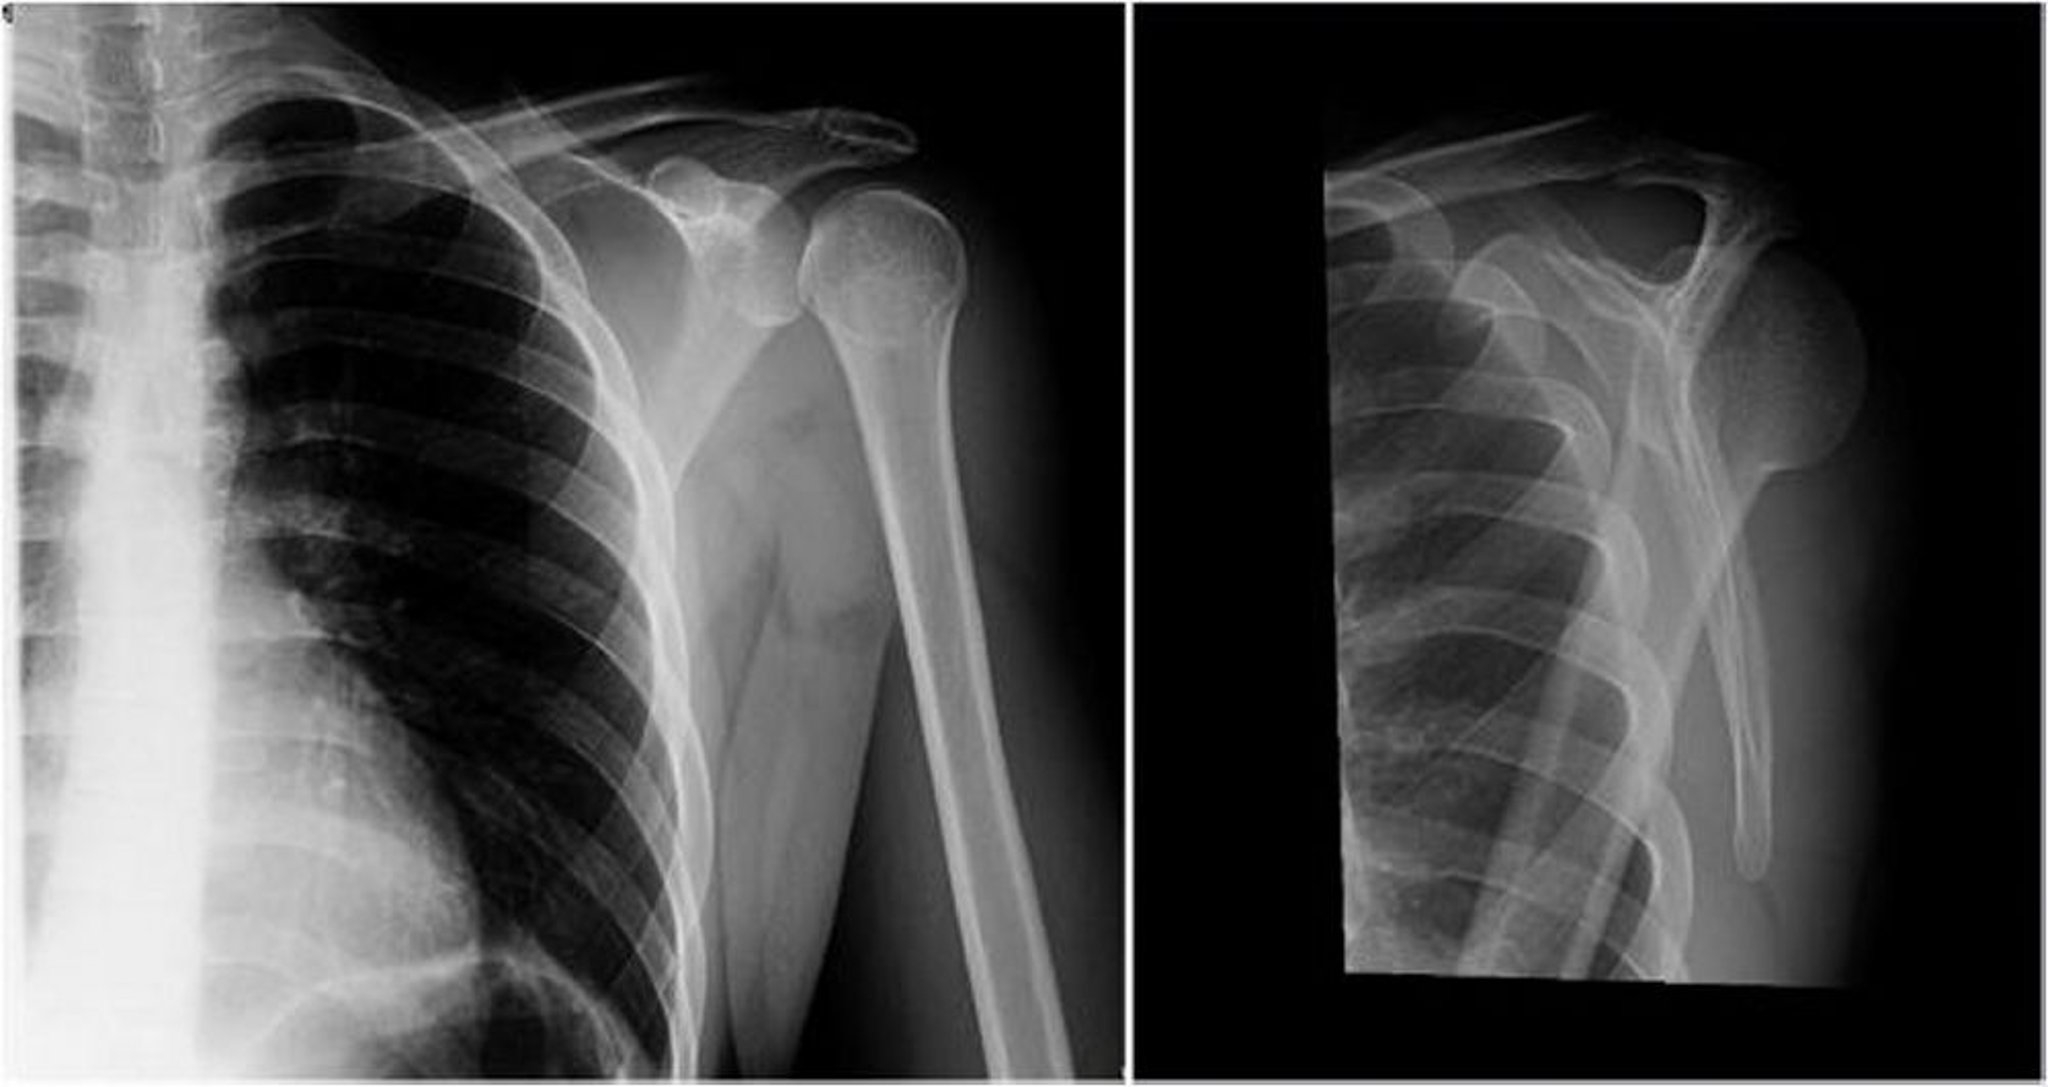

Lussazione posteriore della spalla: proiezione antero-posteriore e a Y [un'incidenza che separa la scapola e l'omero dalle coste]

Nell'immagine di sinistra (incidenza anteroposteriore), la testa dell'omero è ruotata internamente, con il riscontro del segno lampadina o del segno del cono di gelato (le proiezioni delle tuberosità omerali [grande e piccola] non sono visibili), il che suggerisce una lussazione posteriore. Nell'immagine a destra (vista a Y [un'incidenza che separa la scapola e l'omero dalle coste]), la testa omerale è posteriore alla fossa glenoidea, il che dimostra l'esistenza di una lussazione posteriore.

Image courtesy of Danielle Campagne, MD.